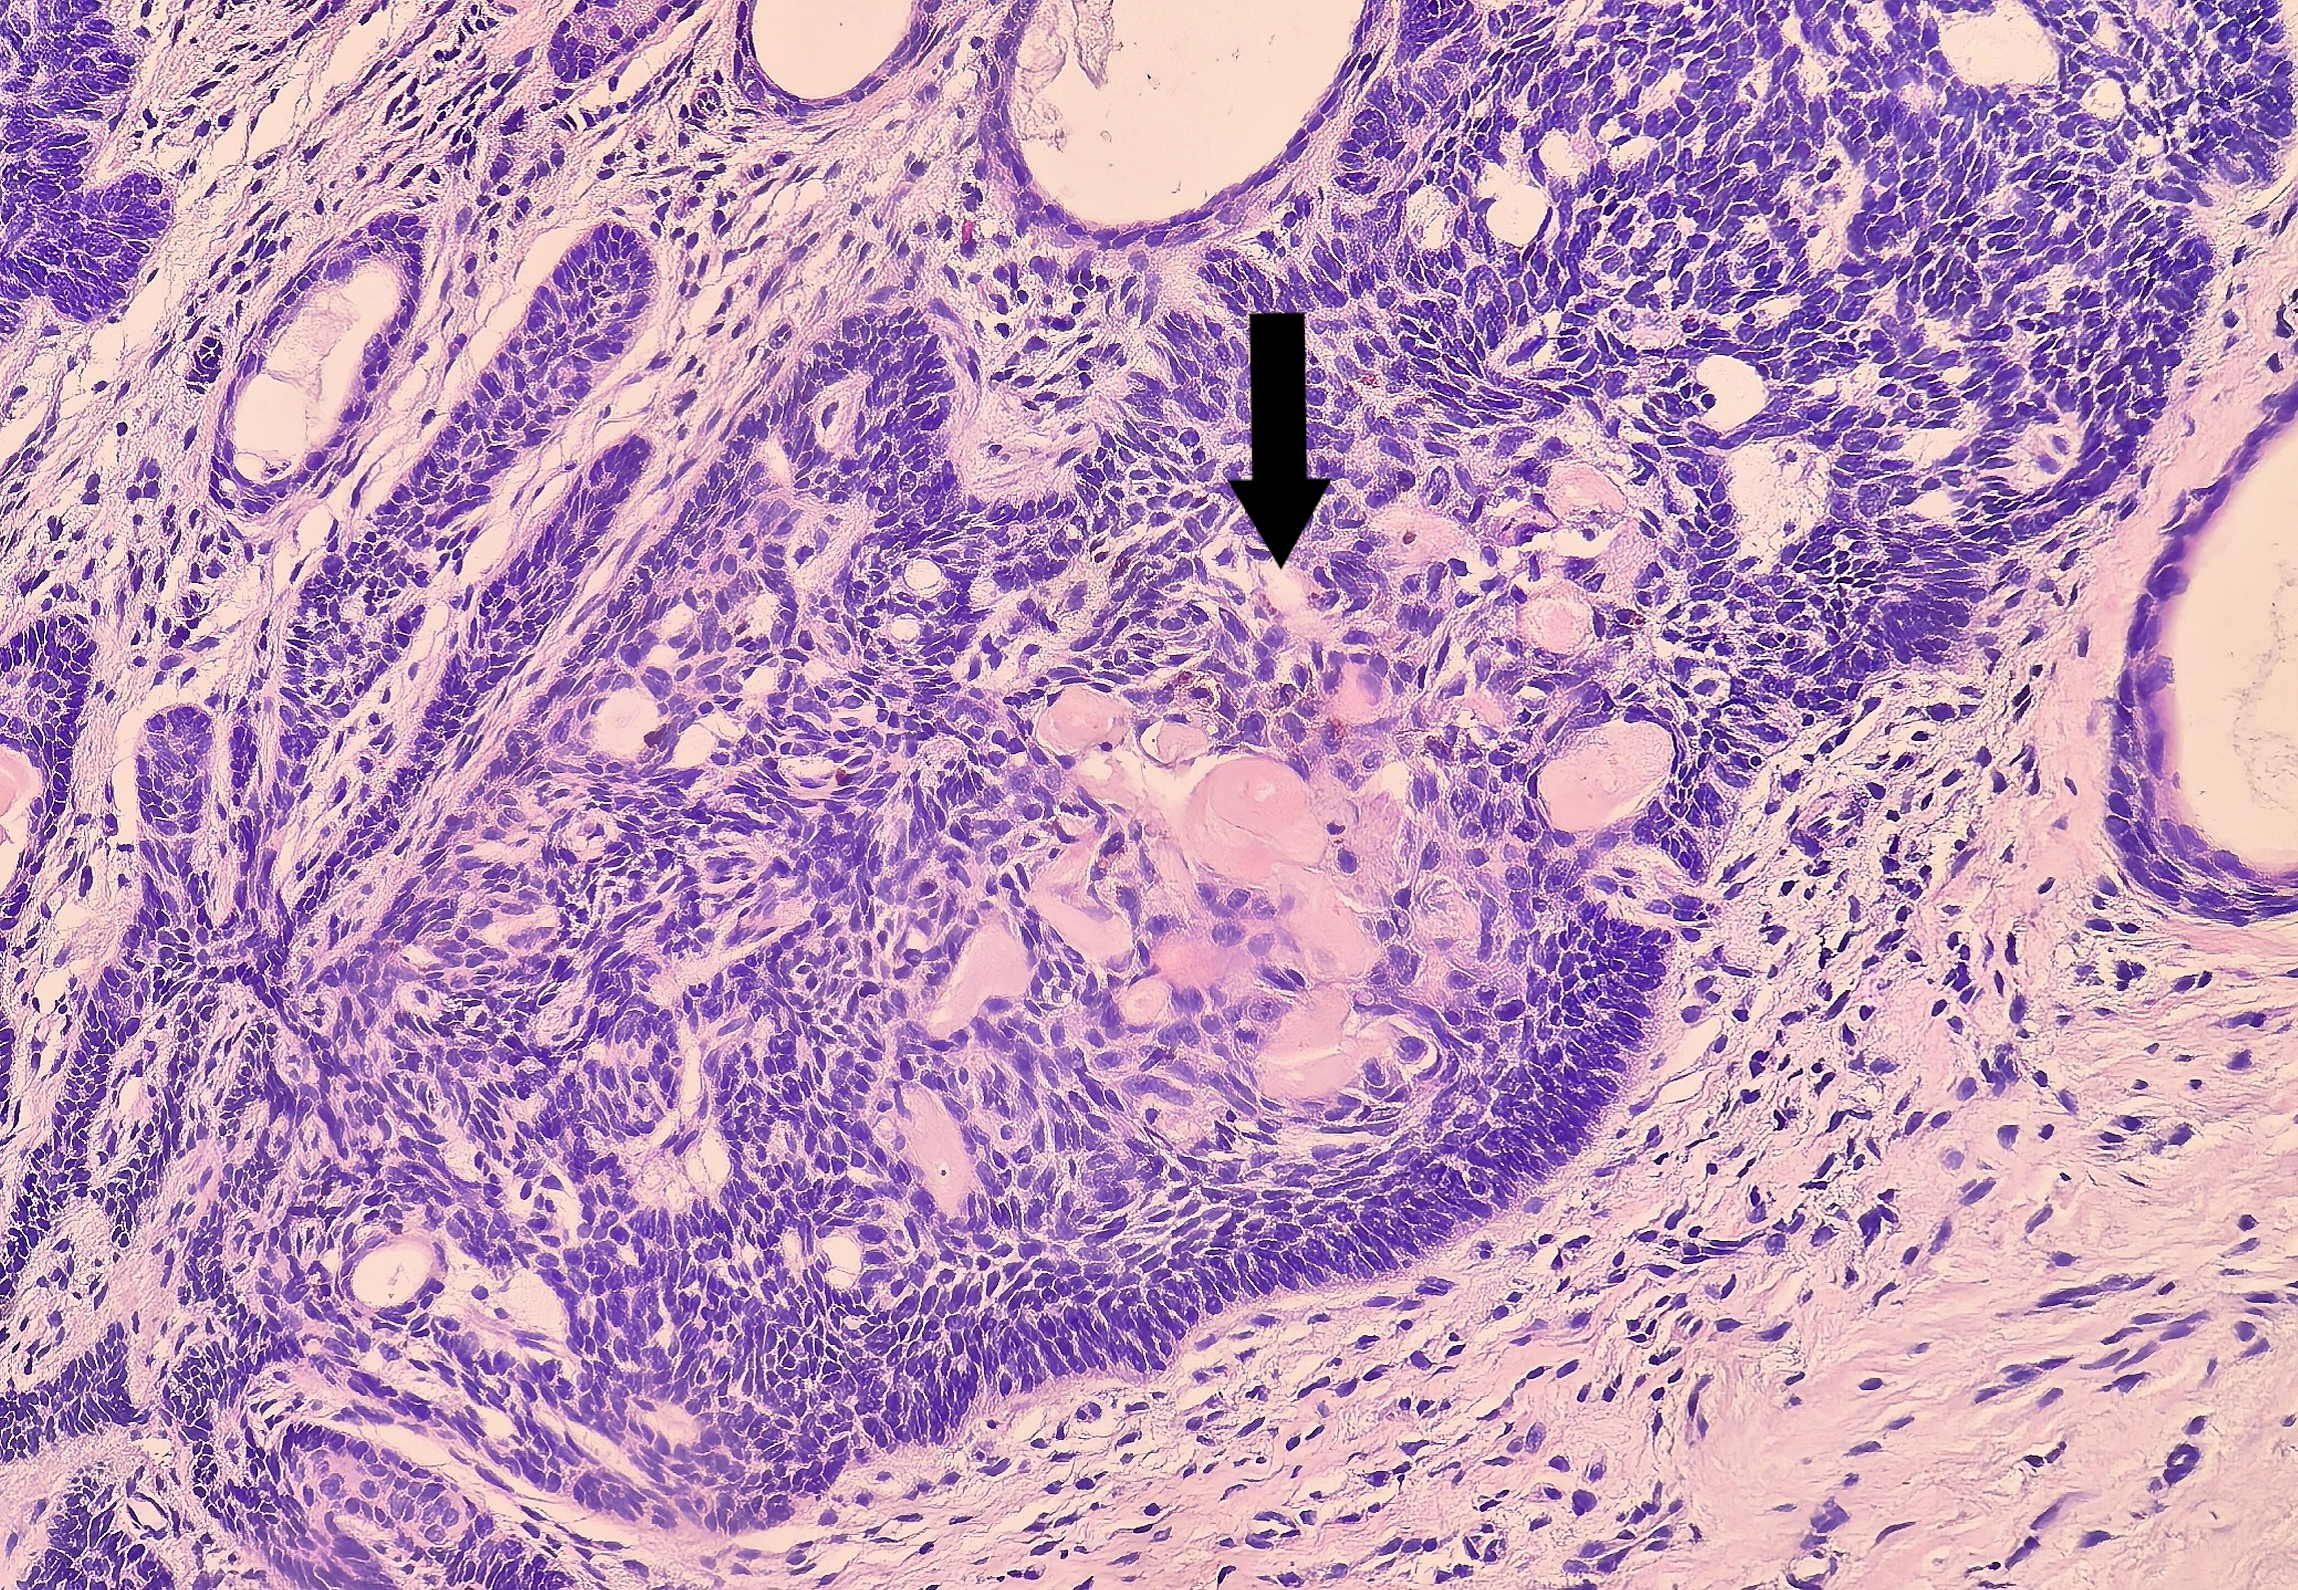

部分基底细胞样巢团可见鳞状分化(图6、7)

本病例最显著的特征是间质可见广泛的骨样基质,呈均质,粉染的不规则编织状存在,可见骨陷窝样结构(图8、9),与肿瘤上皮穿插交错存在。